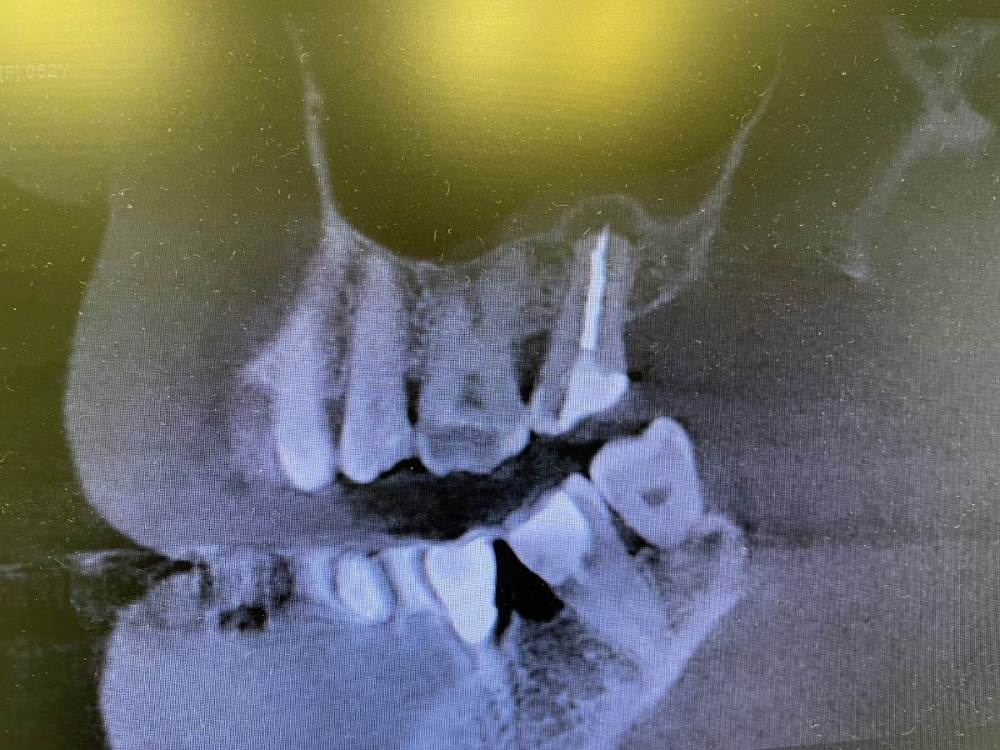

Кирилл Якимов Опубликовано 5 мая, 2022 Поделиться Опубликовано 5 мая, 2022 Добрый день, дорогие коллеги! Я начинающий врач, очень нужна конструктивная критика) 2.7 зуб, каналы лечили несколько лет назад(пациентка точно не помнит). Зуб не беспокоит. Сделал прицельные снимки + КТ. Есть очаг перирадикулярной деструкции+гуттаперча за апексом+резорбция. Принял решение зуб перелечить. Убрал старую пломбу и кариес, гутта в каналах мягкая, распломбировал довольно быстро Profile 25.06 25.04 и желтый Mtwo со стеночек+активация гипохлорита 3% U-file 15 стальным. Из-за апекса гуттаперчу вытащил H-file. В первый визит расширил до 70 K-file. Длина обеих каналов 18мм. Оставил кальций на 2 недели. Коллега микроскопист говорит, что нужно делать пробку МТА, дальше обтурация гибридной методикой, затем коронка и контрольное КТ через 6 мес. Подскажите пожалуйста, как и чем все таки лучше пломбировать такой зуб и какой наиболее вероятный прогноз? Кто что думает, в чем может быть причина такой резорбции? Ссылка на комментарий